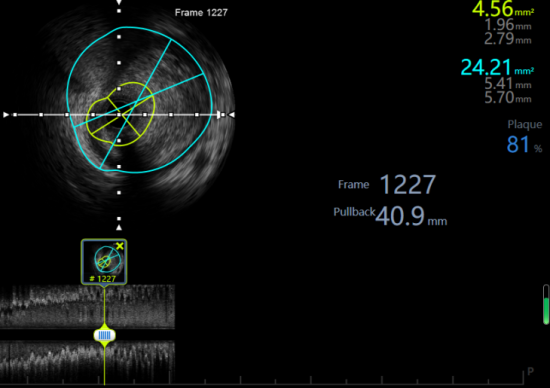

面对患者无法使用造影剂的客观限制,心内九李赫主任及孙永波医师经全面评估,最终确定采用 “零造影剂冠状动脉支架植入术” 这一解决方案。手术将完全依赖血管内超声(IVUS)作为核心引导技术。IVUS通过送入血管内的微型超声探头,能够直接获取血管横截面的高清图像,清晰显示血管壁的结构、斑块的形态与管腔的大小。李赫主任团队在导管室孙敬皓医师及导管室护理团队的配合下,将依据这些实时、精确的腔内影像信息,替代传统的造影剂显影,完成从病变评估到支架植入的全部操作。

病变精准评估:术中使用IVUS探头对左主干病变进行系统扫描,精确测量病变的长度、血管直径及狭窄程度,为制定手术方案提供关键数据。

支架精准植入:基于IVUS的测量结果以及确定骨性标志,在无造影剂显影的情况下,将支架沿导丝准确输送至目标位置并成功释放。

术后效果确认:支架植入后,立即再次通过IVUS从多个切面进行扫描,确认支架扩张充分、与血管壁贴合良好,并排除血管夹层等并发症。

术后IVUS检查证实,支架在左主干开口精准定位,支架膨胀及贴壁情况良好,手术取得预期效果。患者术后恢复顺利,胸痛症状完全消失,且成功避免了因再次使用造影剂而可能引发的过敏风险。